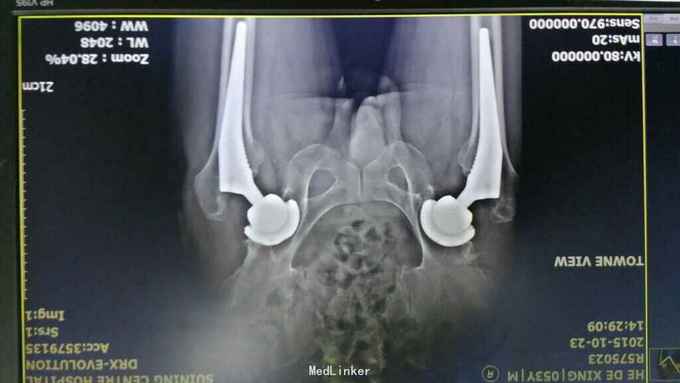

诊断:左全髋关节置换术后关节脱位 双侧全髋置换术后 治疗:急诊手法复位

术后复查位置好 考虑左髋臼前倾角度太小?